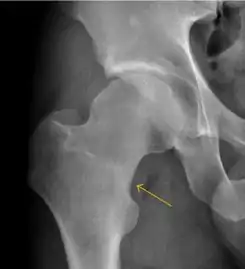

MRI has been shown to have 100% sensitivity and specificity in prospective studies of occult hip fractures. These fractures were diagnosed by bone marrow edema and a low signal fracture line, mainly on T1 or T2 weighted images (Figure 10).[1]

Figure 10:

Stress femoral neck fracture in a young athlete barely visible in X-ray film as a sclerotic line (arrow)[1]

In this case, Tc 99 scintigraphy shows a band of uptake[1]

Furthermore, T1 (left) and DP fat saturated (right) weighted MR images showed the fracture line and a pattern of edema.[1]